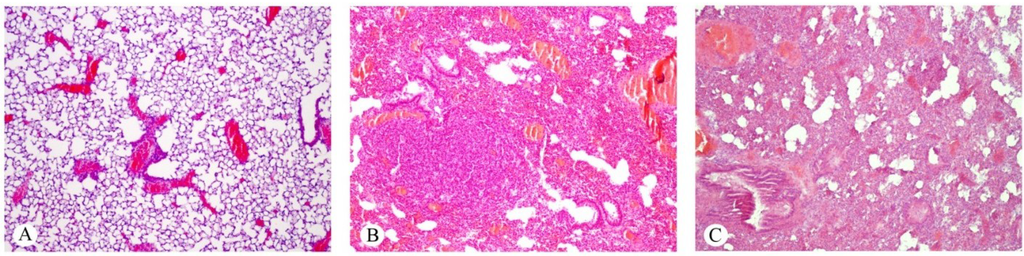

2.2. Effects on the Intestines